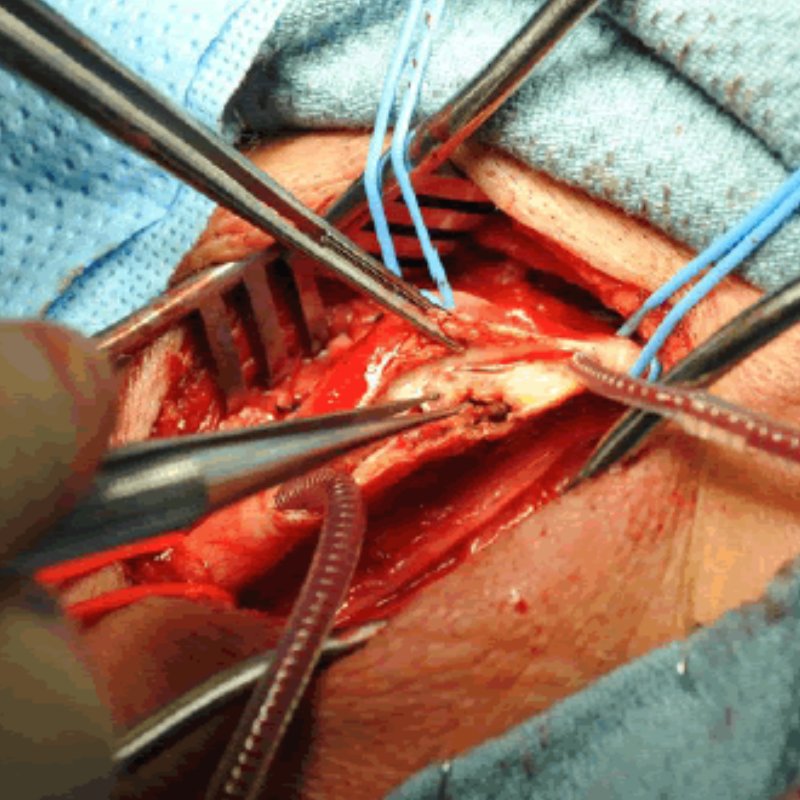

Κατά την διάρκεια της ενδαρτηρεκτομής καρωτίδας, ο αγγειοχειρουργός διενεργεί μια τομή στον τράχηλο. Η επέμβαση μπορεί να γίνει με αποκλεισμό της κυκλοφορίας, με ειδικές κλάμπες, ή με διατήρηση της αιμάτωσης στον εγκέφαλο κατά την διάρκεια της επέμβασης (με χρήση shunt). Ακολουθεί διάνοιξη του πάσχοντος αγγείου, αφαίρεση της αθηρωματικής πλάκας και συρραφή του αγγείου, συνήθως με τη χρήση patch.